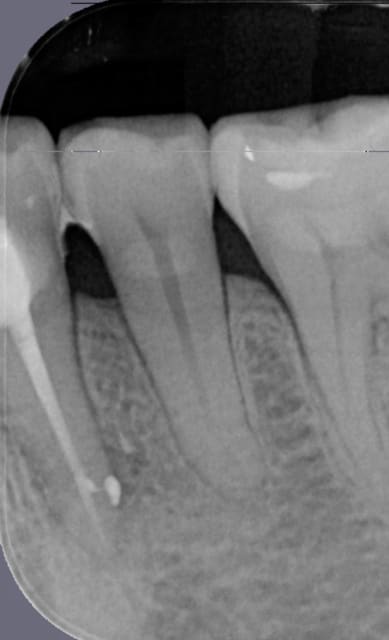

Bon avant et après GC. Sur les canaux en 8 balèzes c'est chiant de condenser et d'avoir cette sensation de remontée du GC.( GC de 40)

1 ir7utf - Eugenol

2 lu9rz8 - Eugenol

Ok! Densité améliorée de l'obturation.( previsible heureusement)

Rien de plus dans ce cas précis au niveau du 1/3 apical.